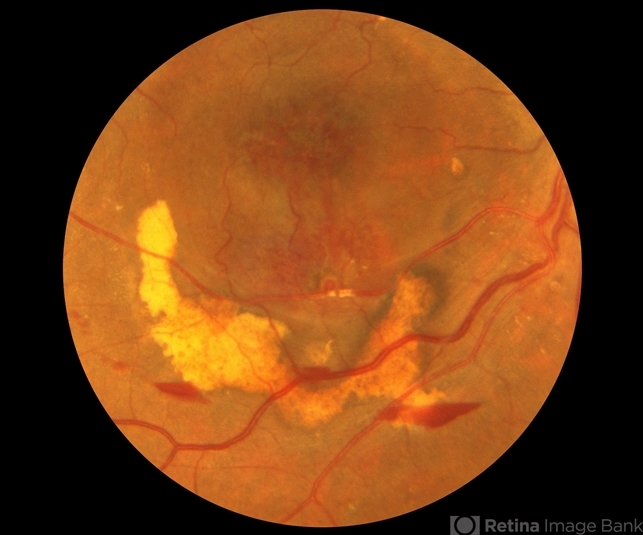

- reabsorbing subretinal hemorrhage, hyaloidotomy

- Reabsorbing subretinal hemorrhage, s/p YAG, hyaloidotomy.